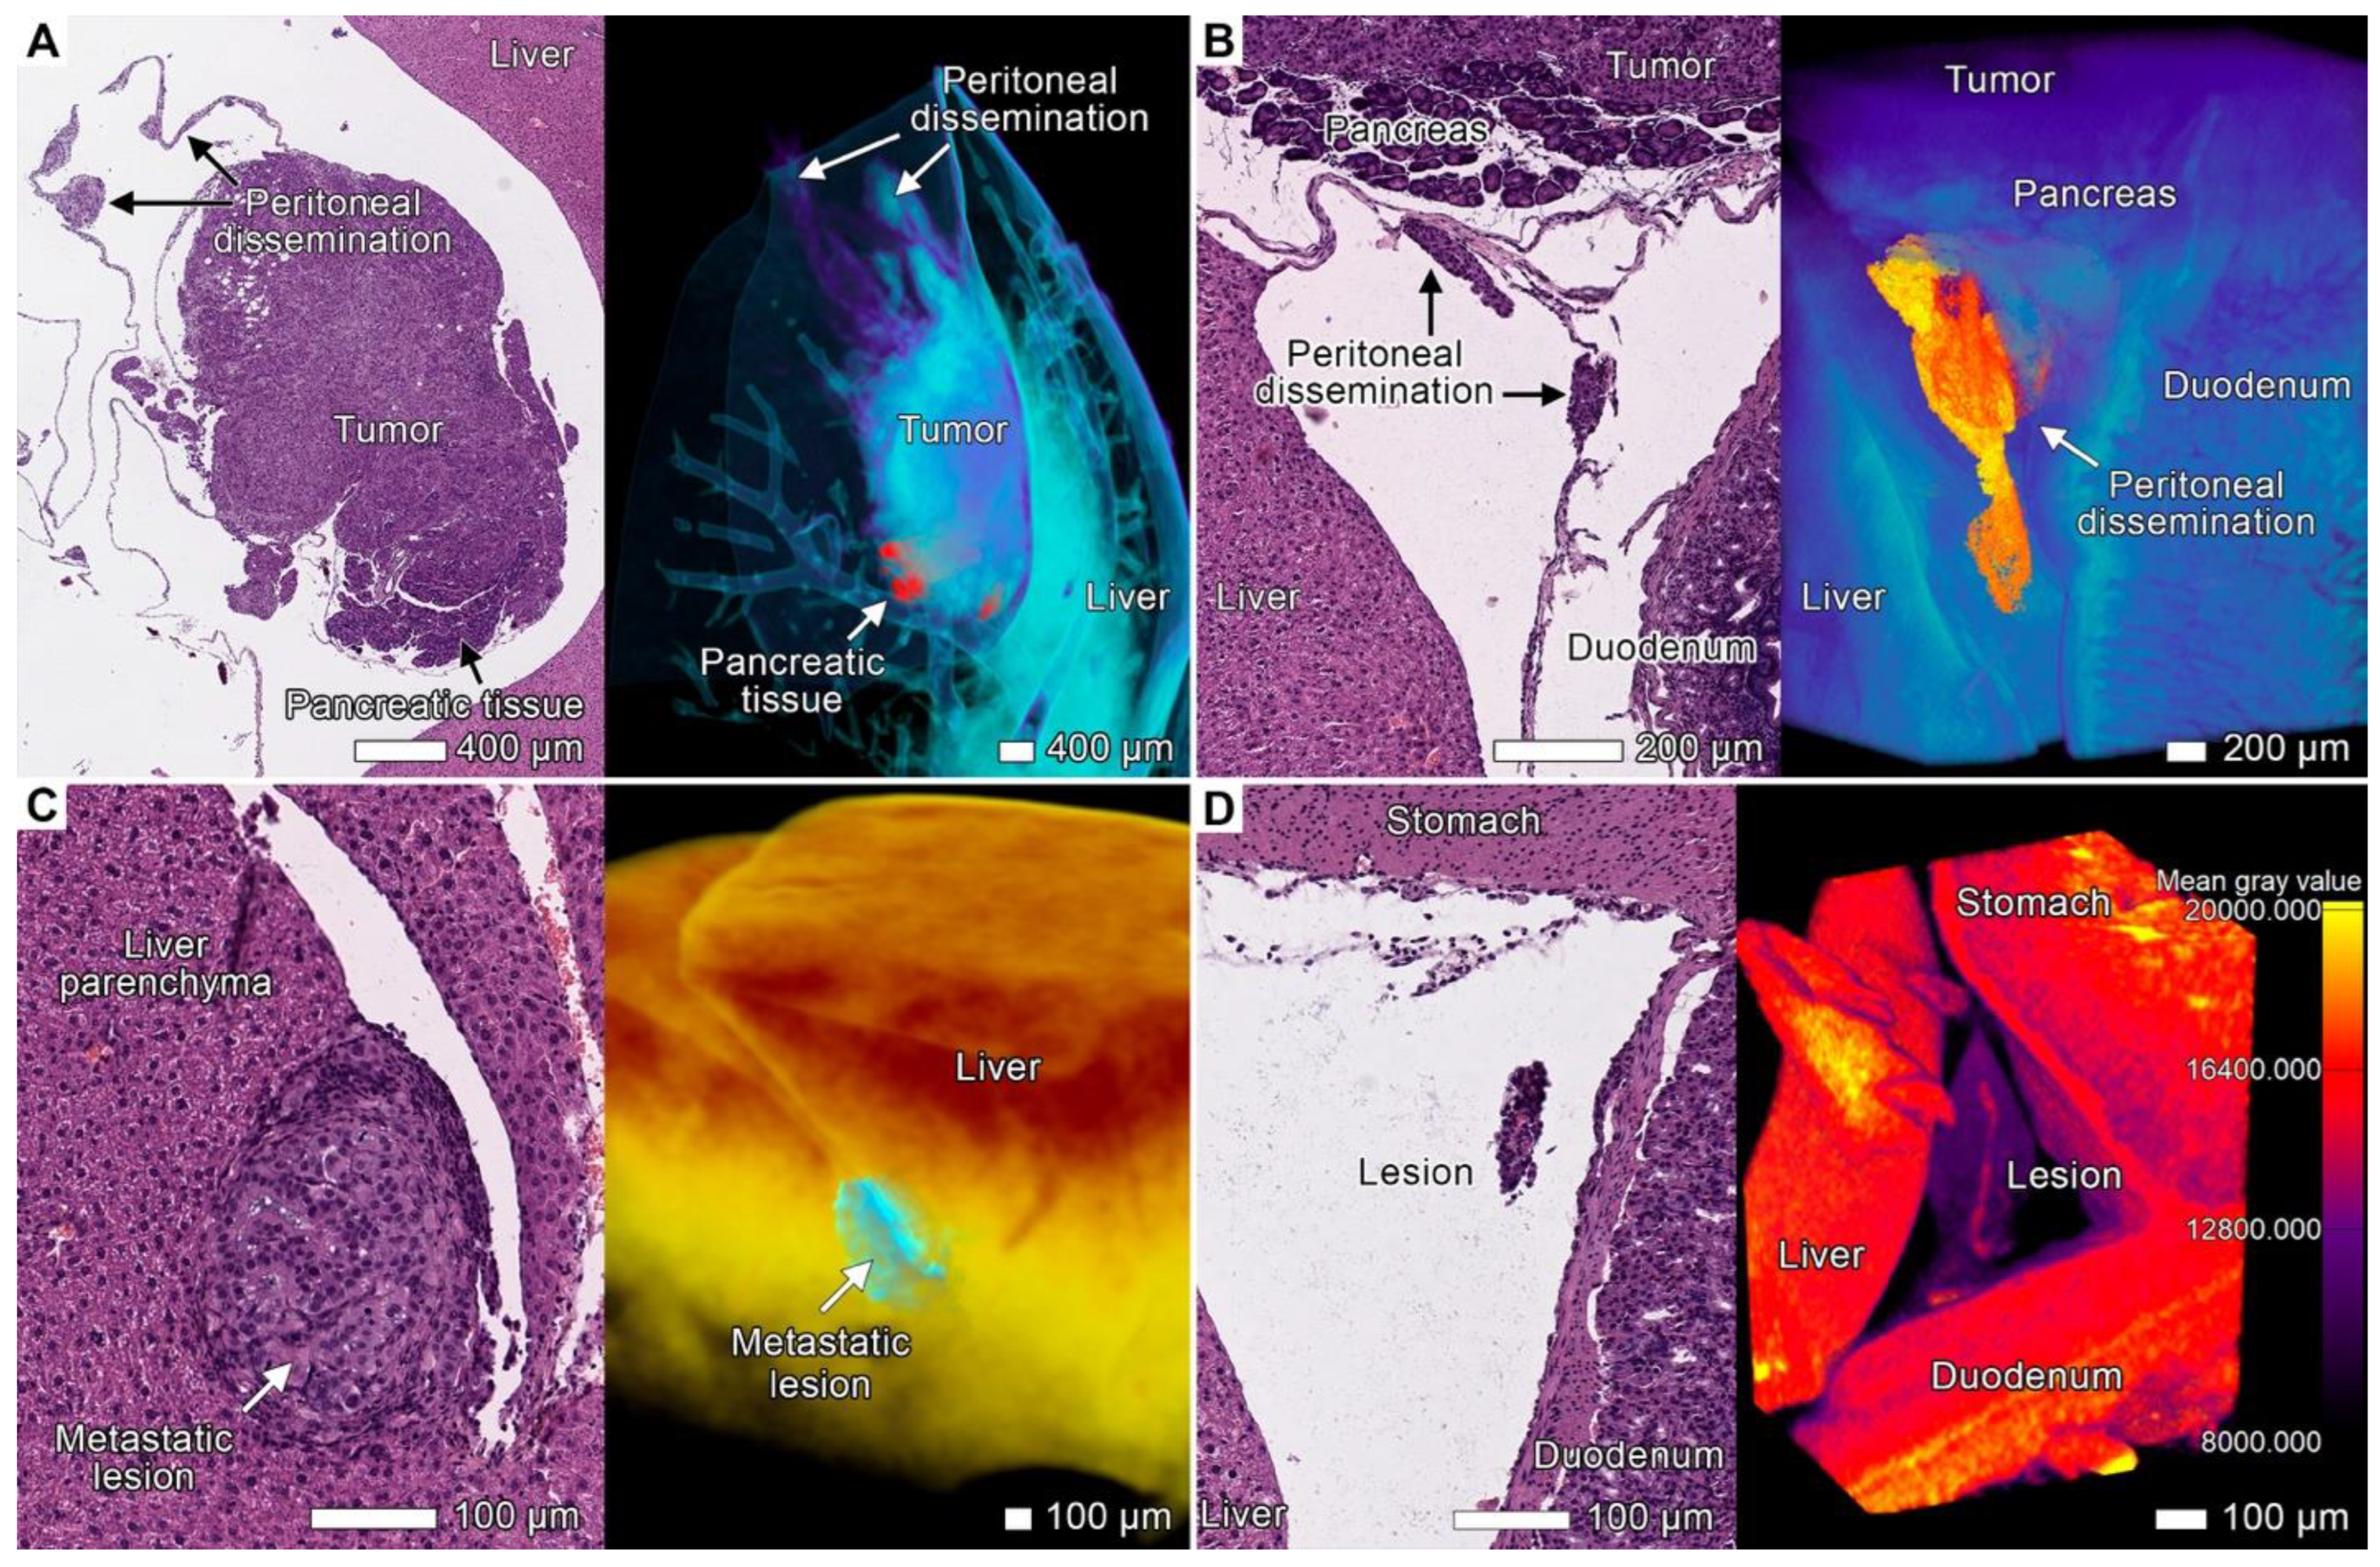

3.6. Peritoneal Dissemination

4.8. Peritoneal Dissemination